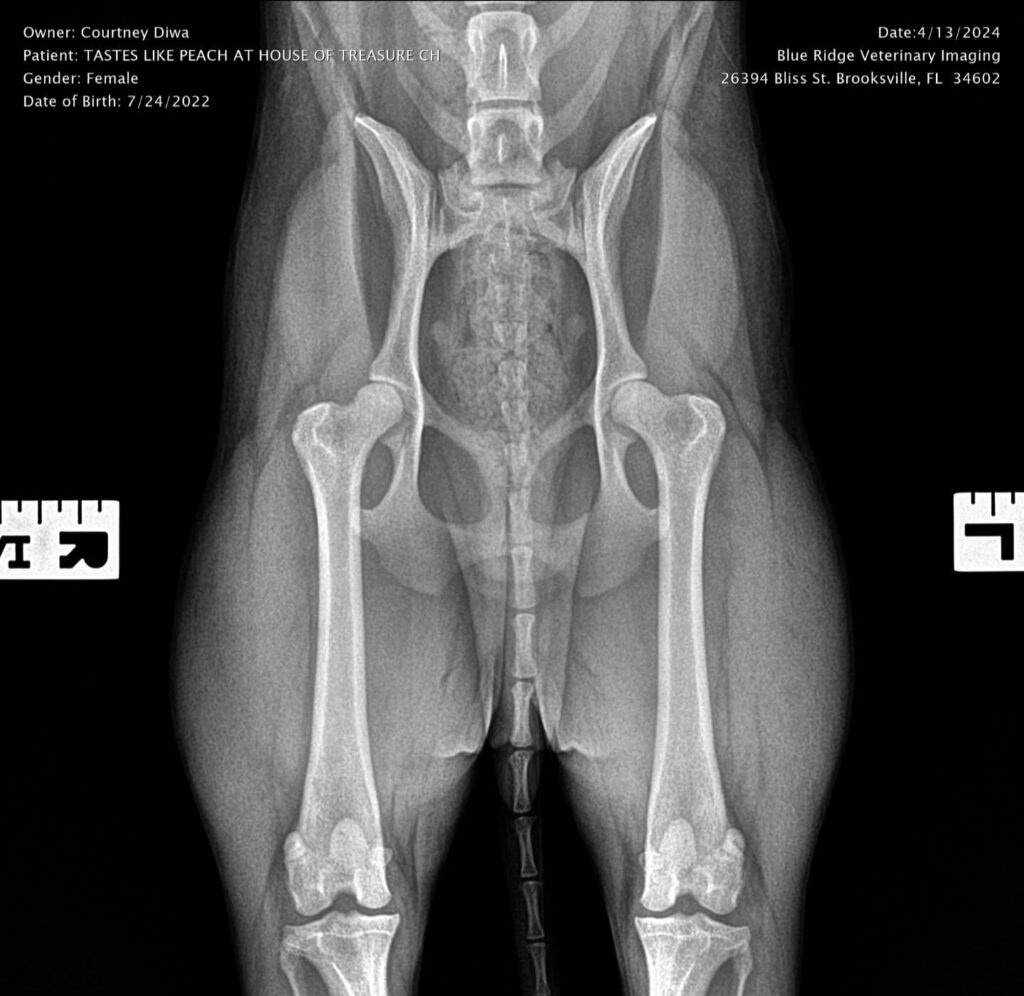

Titles & Health Certificates